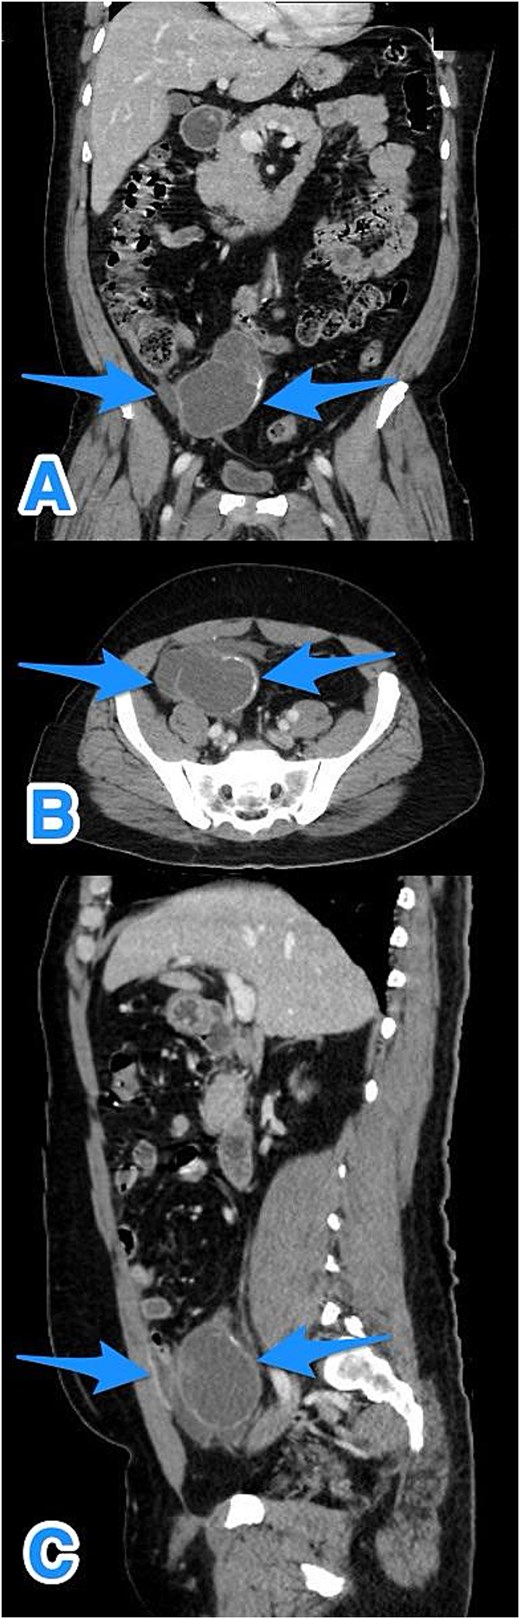

A contrast-enhanced computed tomography (CT) scan of the abdomen and pelvis demonstrated a fluid-filled, markedly dilated appendix (5.2 cm) with peripheral calcification, particularly at the tip. A focal wall defect was observed on the anterior aspect of the appendix, with associated loculated free fluid, suggestive of rupture (Fig. 1). No significant lymphadenopathy, hepatic, or peritoneal disease was identified. These findings were consistent with a ruptured appendiceal mucocele with localized peritoneal fluid.

Multiview contrast-enhanced CT images of the perforated appendix with associated free fluid: (A) coronal view, (B) axial view, and (C) sagittal view (arrows).